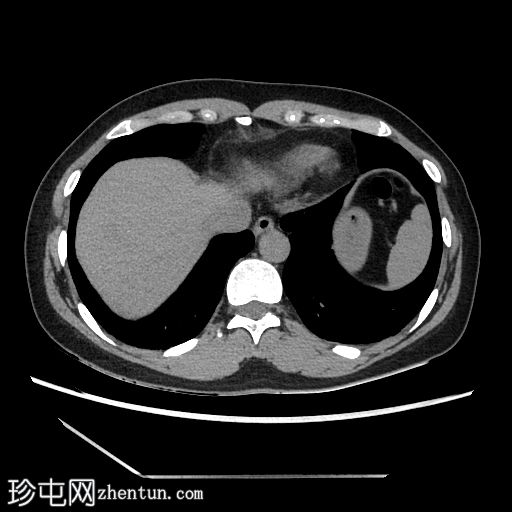

2.jpg

轴向C+期

动脉期

在轴向、冠状面和矢状面上均可见肝5/6段病变。动脉期可见周围结节状强化,门静脉期可见进行性向心性充盈,延迟期亦持续存在。这些表现为肝血管瘤的特征性表现。

然而,目前的CT扫描显示动脉期呈周围结节性强化,门静脉期呈进行性向心性充盈,且延迟成像后仍持续存在。这些特征是肝血管瘤的特征。未发现其他肝脏病变。